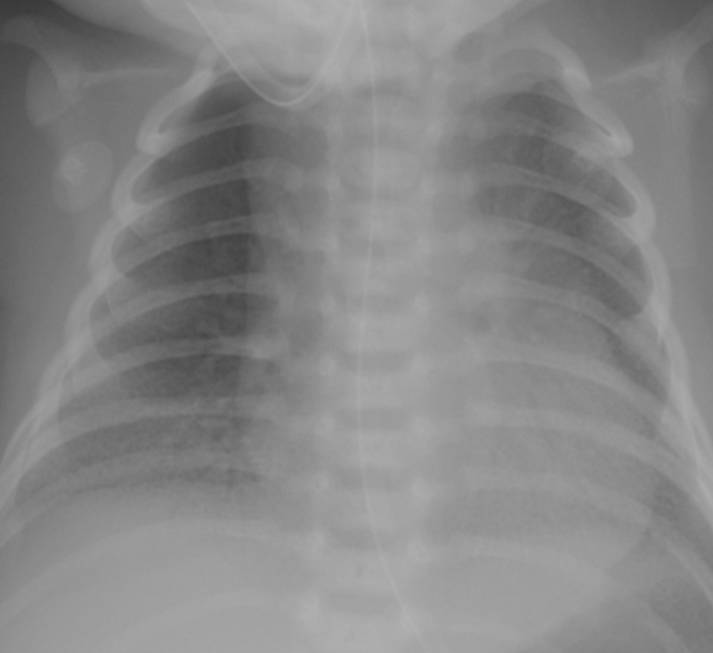

典型胸片結果:

(II-III級肺透明膜病變)